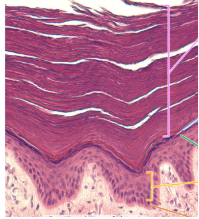

What is this?

Thin skin

thick skin